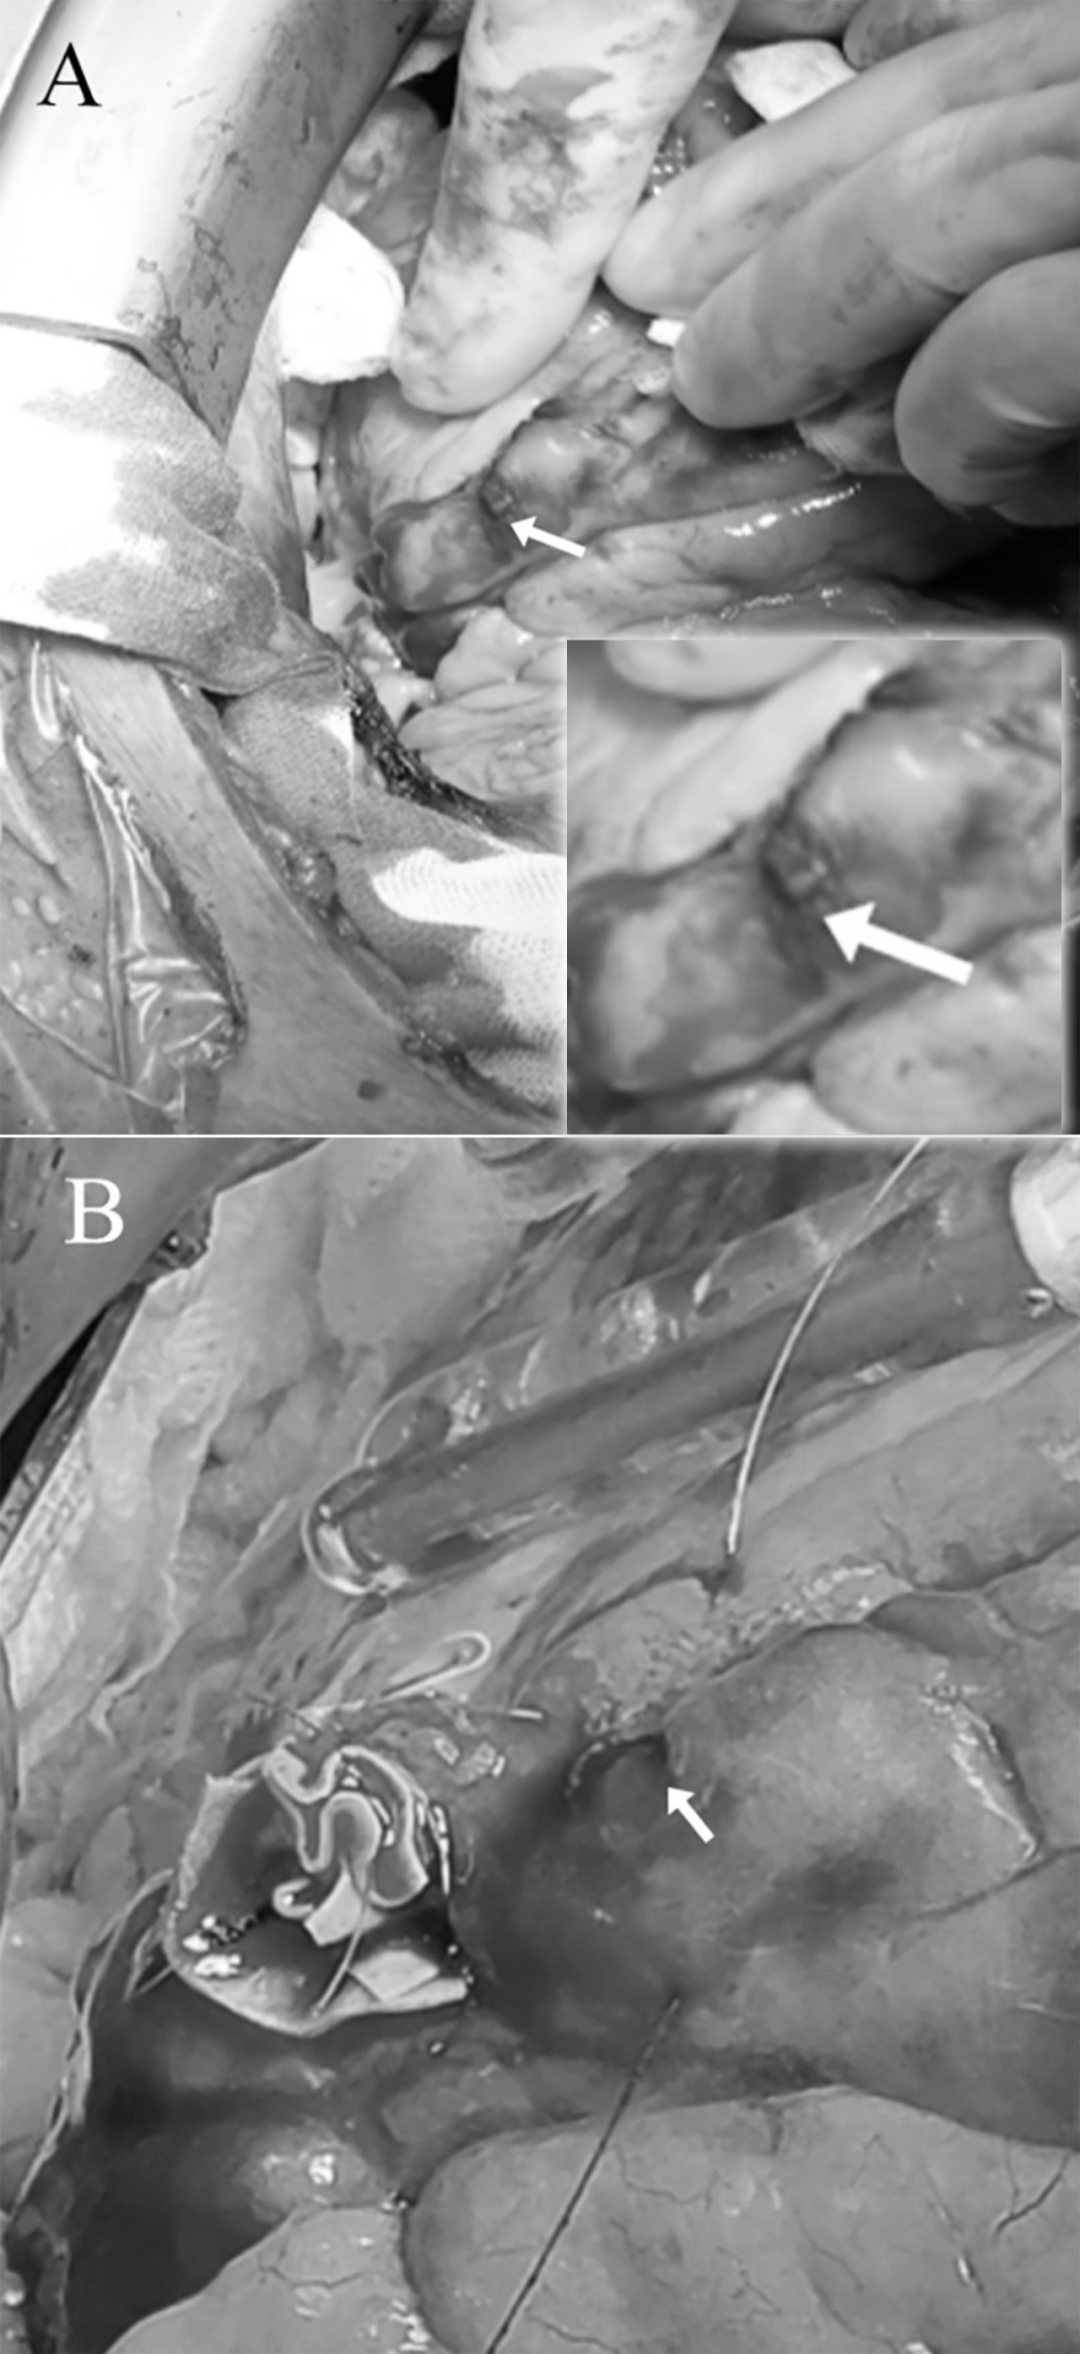

术中探查:对角支远端6mm破口(图4A)

补片修补:心包补片缝合止血(图4B)

图4开胸手术

(A)箭头指向冠状动脉破裂部位(B)箭头指向缝合后未再出血的冠状动脉破裂部位。